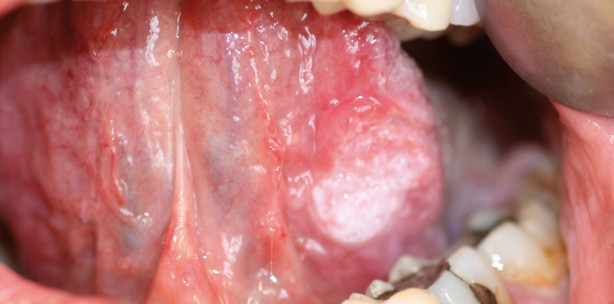

Der klassische Risikopatient für eine bösartige Erkrankung von Mundhöhle oder Lippen ist männlich, über 60 Jahre alt, trinkt gern ein bisschen zu viel, raucht seit Jahrzehnten und kennt wichtigere Dinge im Leben als die Mundhygiene. Sein Glück, dass die meisten Ärzte und Zahnärzte bei ihm zwar schnell an ein Karzinom denken, sein Pech, dass man bei ihm dann selten von ­Früherkennung sprechen kann, weil dieser Patient in der Regel eher lange Zeit indolent ist. Die Früherkennung ist in diesem Bereich aber ganz besonders wichtig, weil es aufgrund der sehr guten Versorgung des Kopf-Hals-Bereichs mit Blutgefäßen und Lymphbahnen schon sehr früh zur Streuung kommt. Es ist nicht ungewöhnlich, dass die Lymphknotenmetastase am Hals noch vor dem Primärtumor im Mund gefunden wird, sodass der aufmerksame Arzt oder Zahnarzt auch hier bereits hellhörig werden sollte. Der Primärtumor ist oft noch klein, und er liegt bevorzugt an selten inspizierten Stellen wie unter Zunge, also am Mundboden oder an der Zungenunterseite, an den Gingivarändern lingual, an den Wangeninnenseiten oder der Innenseite der Oberlippe. Auch gehen die Tumoren im Bereich der Mundhöhle oft aus Präkanzerosen hervor, am häufigsten aus Leukoplakien oder Virusdysplasien, oder sie gedeihen auf dem Boden einer primär harmlosen Veränderung wie eines Reizfibroms. Da der Patient und auch der Behandler diese genannten Veränderungen schon länger kennen, verändert sich natürlich auch die Aufmerksamkeitsschwelle und etwaige „Veränderungen der Veränderung“ werden gar nicht oder erst spät registriert.

Sollte eine Veränderung zunächst nur kontrollbedürftig erscheinen, gilt, dass Zeiten für eine zu erwartende Abheilung oder Verbesserung kurz angesetzt werden sollten, wenn die Möglichkeit einer Malignität besteht, also lieber engmaschig kontrollieren und zügig überweisen als großzügig zuwarten. Für einen selbst zum späteren Vergleich und auch für eine Überweisung ist eine genaue Beschreibung des Befundes sehr wichtig, die Art der Effloreszenz (Makula, Papel, Vesicula, Bulla, Erosion, Ulcus, Rhagade, Atrophie, Narbe), die Färbung und deren Intensität (intensivrot, schwachrot, weißlich, weiß, gräulich etc.), Zahl und genaue Verteilung bei mehreren Veränderungen, spezifische Kennzeichen (netzförmig, gestielt, erhaben),  die Größenausdehnung (in mm) sowie der Palpationsbefund der Veränderung selbst und der Lymphknotenstationen. Dabei ist es nicht wichtig, immer genau die richtigen Fachtermini zu beherrschen, sondern die Beschreibung muss (egal ob trocken oder fanta­sievoll) einfach nachvollziehbar sein. Bewährt hat sich auch die bildgebende Archivierung. Im Zeitalter der Intraoralkameras und günstig gewordenen Spiegel­reflexkameras sowie den immer größeren Speichermöglichkeiten ist dies eine gute und sinnvolle Hilfe, die Schleimhautbefund zu archivieren.